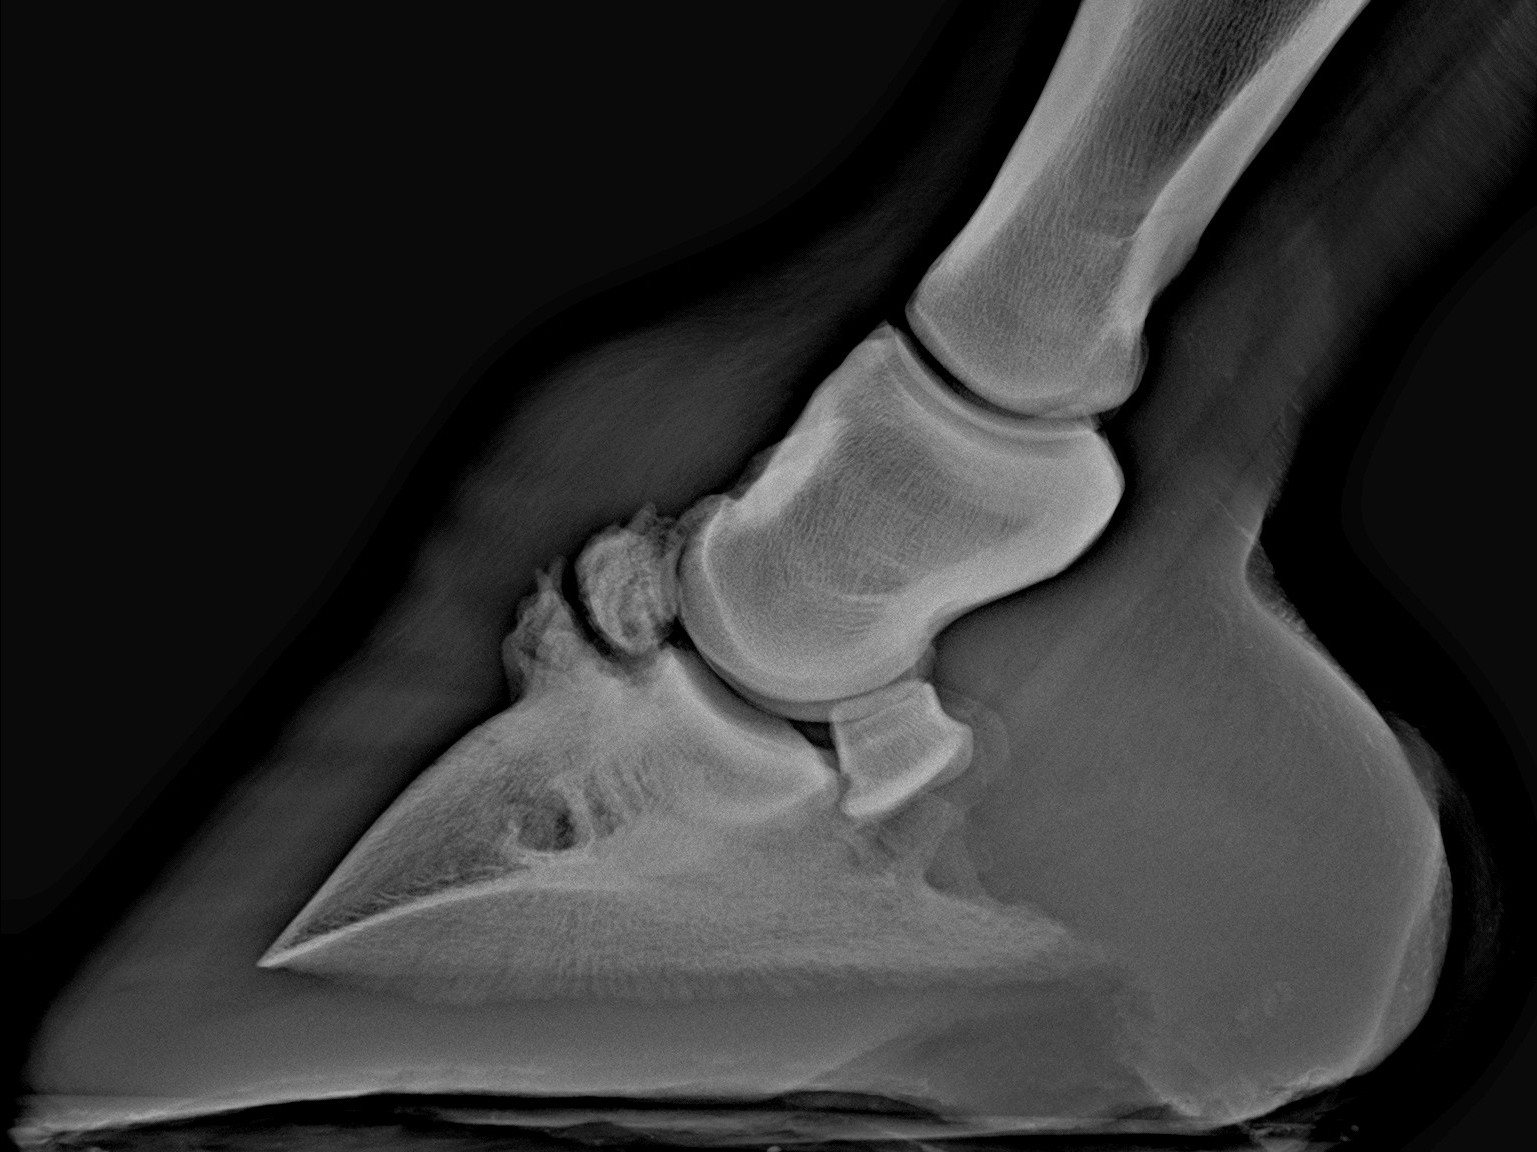

Így néz ki egy egészséges pataízület

Enyhe RTG elváltozások. A nyilak csontfelrakódásokat mutatnak.